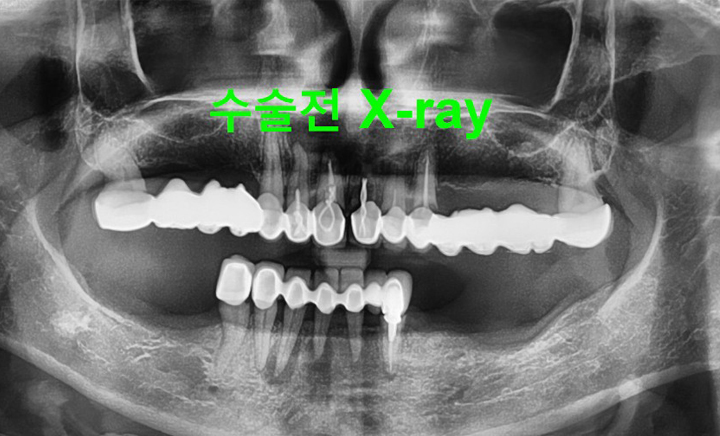

환자분 상태에 따라 임플란트를 2개에서 4개 정도만을 식립하고

그 위에 틀니를 고정시키는 치료 방법

노화나 사고로 이가 전체적으로 없는 경우에는 임플란트가 가장 좋은 치료 방법이나

경제적인 비용 때문에 대부분은 틀니를 하게 됩니다.하지만 틀니를 해도 예전의 기능을 100% 회복하지는 못합니다. 완전 틀니의 경우 보통 10~30%의 기능만이 회복되며 잇몸 위에 얹어지는 구조물이므로 잇몸에 압박을 가하게 되며 이로 인해 잇몸이 부을 수도 있고 심하면 염증이 생기거나 상처가 생겨 곪을 수도 있습니다.

그리고 위턱의 틀니는 입천장이 있어 그나마 고정이 잘되지만 아래턱은 그런 구조물도 없는데다 혀가 자꾸 방해하기 때문에 고정하기가 쉽지 않아 틀니가 움직이는 불편함이 생깁니다. 이러한 틀니의 단점을 보완하고 틀니의 경제성과 임플란트의 기능성을 결합해 만들어진 것이 틀니 임플란트 입니다.